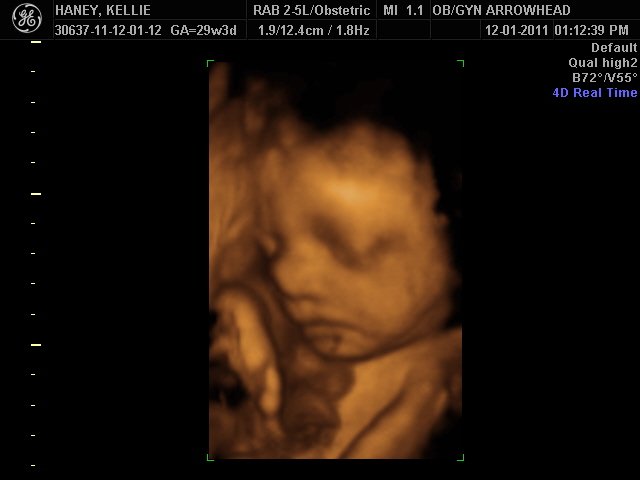

We offer complimentary 3D/4D Ultrasounds to all our OB patients around 30 weeks! The following photos are some examples of our work, shown with permission from our patients.